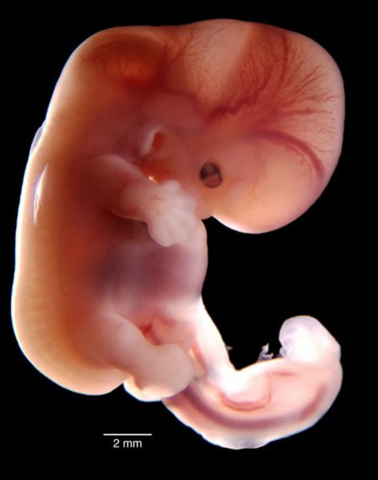

• ETAPA EMBRIONARIA.

El embrión desarrolla órganos y su cuerpo toma un molde pero es sensible a agentes que podrían darle malformaciones.

Es de la cuarta semana hasta la octava.

• 6ª Semana ETAPA EMBRIONARIA

6ª Semana ETAPA EMBRIONARIA

La cabeza crece desproporcionadamente, y los párpados se forman.